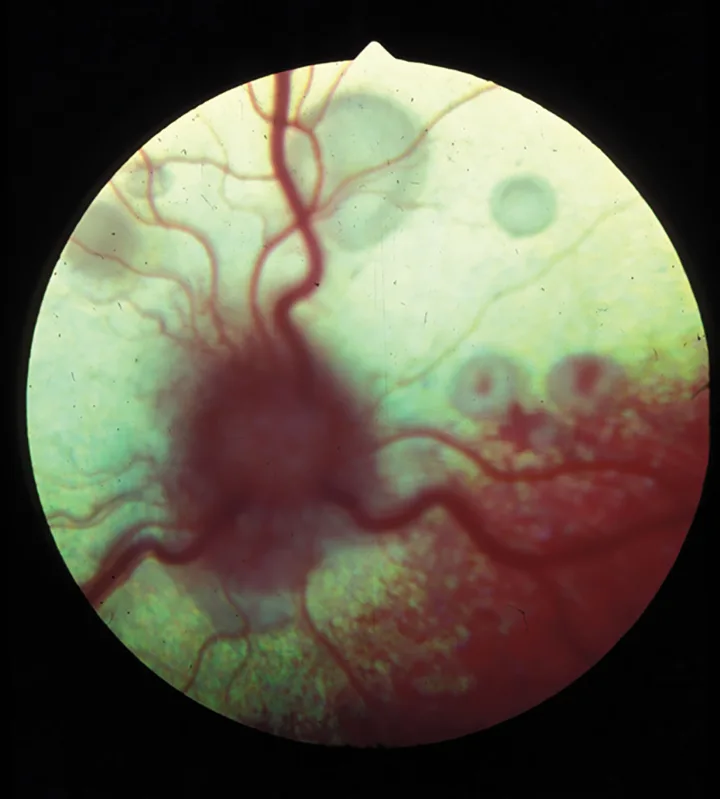

Chorioretinitis appears clinically as a color change or loss of clarity of tissues on fundic examination. With active chorioretinitis, the addition of fluid, protein, and cells within the retina and subretinal tissues will obscure the tapetum or pigment of the choroid (hyporeflective) and may elevate or detach the retina and blur the image. Vascular involvement may result in perivascular cuffing, vasculitis, hemorrhage, and exudate (Figures 1–7). With active chorioretinitis, anterior segment involvement is common, resulting in aqueous flare, miosis, hypopyon, keratic precipitates, cataract, corneal edema, and intraocular pressure (IOP) changes. With chronicity, chorioretinitis leads to focal or diffuse retinal degeneration, tapetal hyperreflectivity, depigmentation, hyperpigmentation, and vascular attenuation (Figures 8–11).

Figure 1.

Active feline chorioretinitis and optic neuritis secondary to systemic cryptococcosis. Multifocal areas of subretinal and peripapillary edema elevate the retina and blur the underlying tapetum.